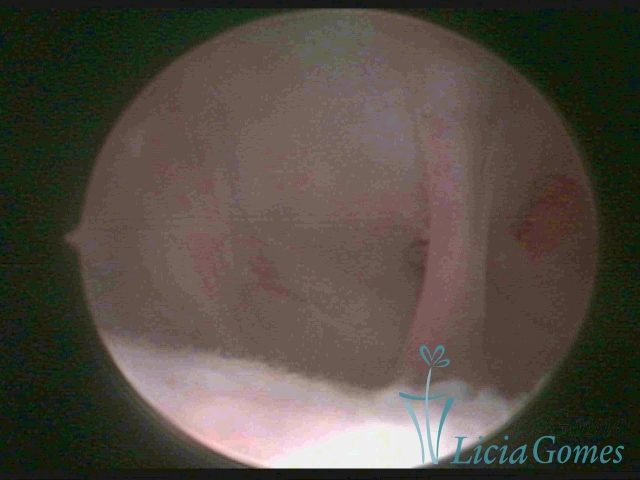

Uterus didelphys

The presence of two uterine cervices and a double vagina, similar to unicornuate uteri, with a normal covering of endometrium.